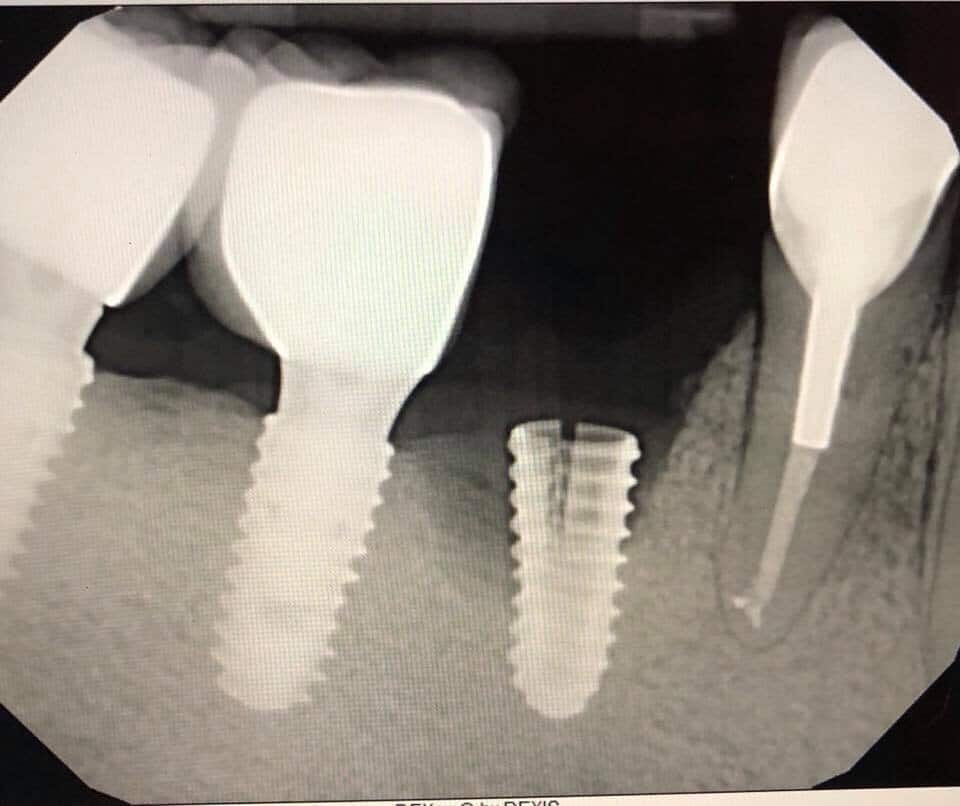

Khi cấy ghép Implant ở hàm dưới, đặc biệt là vùng răng hàm, nếu bác sĩ đánh giá sai vị trí hoặc độ sâu khoan, mũi khoan có thể chạm hoặc xâm lấn vào dây thần kinh răng dưới. Hậu quả có thể gây tê môi, má, cằm hoặc giảm/mất cảm giác vùng mặt, ảnh hưởng lớn đến sinh hoạt hàng ngày của bệnh nhân.

Vị trí đặt trụ cấy ghép có nguy cơ xâm phạm dây thần kinh răng dưới (mũi tên).

Nguyên nhân thường gặp là do thiếu phim chụp CT 3D, không sử dụng máng hướng dẫn phẫu thuật hoặc kinh nghiệm lâm sàng của bác sĩ chưa đủ để xử lý các ca xương hàm phức tạp.